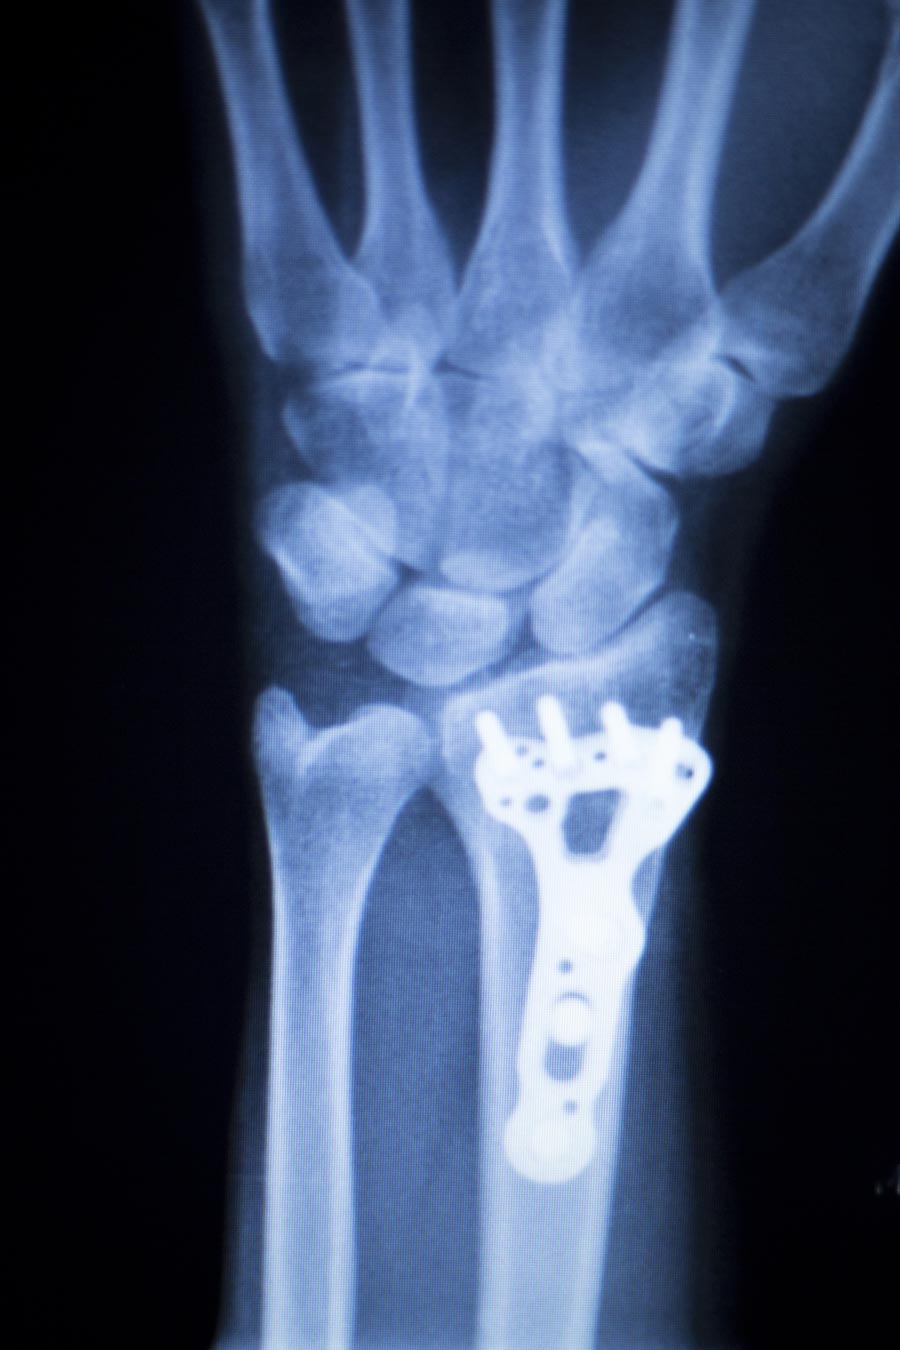

Wrist replacement, also referred as wrist arthroplasty, is a surgical method that removes a damaged portion of the wrist joint and replaces it with artificial implants or prosthetics. These prosthetics are made of silicone, polyethylene, titanium, or pyrocarbon, which will provide an improved range of motion and greater stability to the wrist.

- The prosthesis is then inserted in place and tested for its range of motion.

- The prosthesis is fixed in place using bone cement.

- The carpal bones are inserted back in position and screwed well.